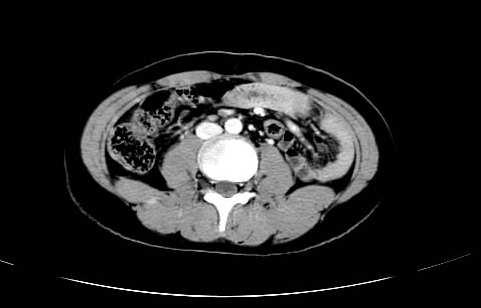

女 16岁  右上腹痛一天,无其他不适

右下腹巨大肿快,密度不均匀,内见坏死低密度区,边界清楚,与周边胀器明显有分界,未见强化,多考虑来源于间叶组织的良性肿物.

我坚决反对您的观点,该病例定位:横结肠肝曲与升结肠之间的肠系膜及部分肠壁。请看下图:

病灶巨大,少部分向肠腔内生长,大部分向长腔外生长。其密度不均匀,增强显示明显不均匀强化,并见有大片状始终不强化的不规则坏死液化区。虽然病灶中上部形态尚可,病人又如此年轻,但中下部形态、密度、强化特点强烈提示为恶性病灶。综上,我考虑本病例为:恶性胃肠道间质瘤。